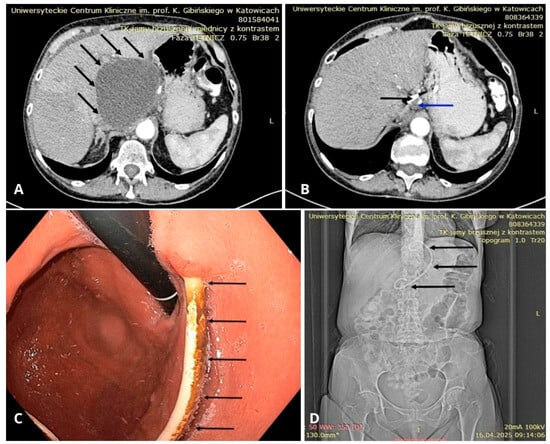

4.1. Percutaneous Drainage (PCD)

6. Endoscopic Drainage of PPCs

6.12. Endoscopic Ultrasound (EUS)

6.14. Transabdominal Ultrasound and CT Imaging